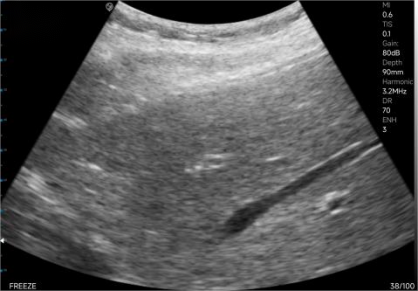

The left image shows the normal depth, and the right image shows the magnified view.